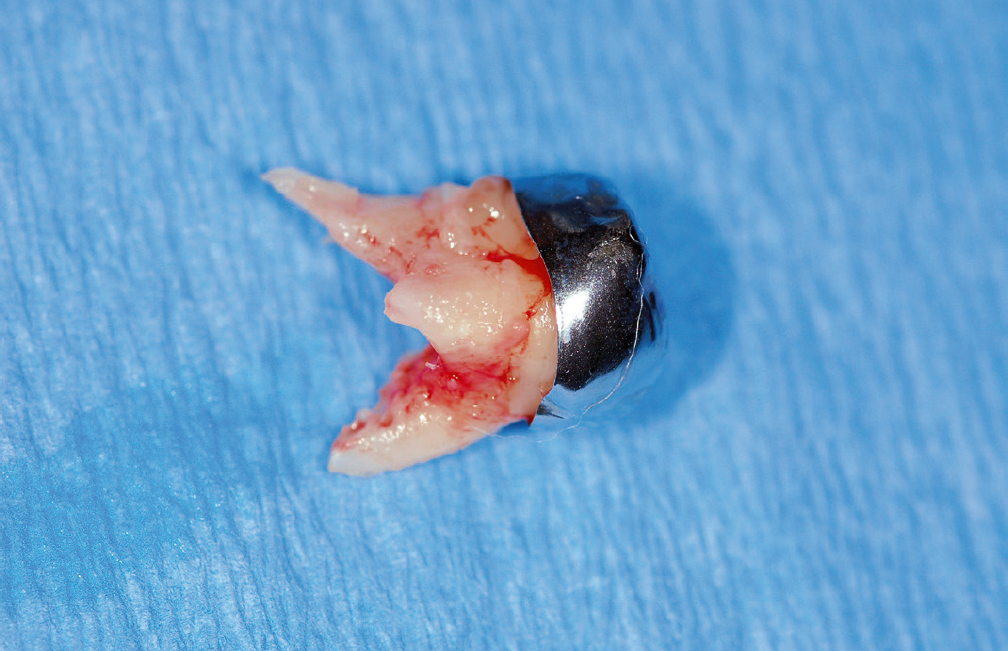

Die meisten lokal begrenzten odontogenen Infektionen werden ambulant therapiert. Bei einer fortschreitenden Entzündung mit Weichgewebsbeteiligung, z. B. durch eine akute oder chronische apikale Parodontitis ausgelöst, treten bei odontogenen Infektionen die typischen Entzündungszeichen Rubor, Tumor, Calor, Dolor und Functio laesa auf. Abhängig von der odontogenen Ursache der Infektion unterscheiden sich die lokalen klinischen Symptome und Ausbreitungstendenzen. Bei einem Infiltrat oder einer lokalen odontogenen Infektion kommt es zu einer enoralen Schwellung, die sich, je nach ursächlichem Zahn, in verschiedene Regionen ausbreiten kann (Abb. 1 bis 3). Besonderen Stellenwert nehmen nicht abgeschlossene endodontische Therapien und Karies profunda als Ursache für eine odontogene Infektion ein und steigern das Risiko, eine odontogene Infektion zu entwickeln. Eine ausführliche Anamnese ist notwendig, um eventuell bestehende Risikofaktoren, z. B. ein nicht eingestellter Diabetes mellitus, Immunsuppression, für eine Ausbreitung der odontogenen Infektion erkennen zu können. Die initiale Einschätzung, ob eine Ausbreitungstendenz besteht, wird häufig durch den Hauszahnarzt gestellt. Um diese Einschätzung durchführen zu können, ist neben der Anamnese eine extra- und enorale klinische Untersuchung notwendig. Hierbei soll laut S3-Leitlinie „auf Zeichen der Ausbreitungstendenz“ geachtet werden, wie z. B. Einschränkung der Mundöffnung, Druckschmerz am Kieferwinkel/Augenwinkel (V. angularis), extraorale Schwellung (Ist der Unterkiefer durchtastbar?), Schluckbeschwerden, Atemnot, angehobener Mundboden, kloßige Sprache, Fieber, Exsikose“11. Die chirurgische Entlastung einer lokal begrenzten odontogenen Infektion steht weiter an erster Stelle der Therapie (Abb. 4 bis 7). Entleert sich Pus und liegen keine Risiken von Seiten des Patienten vor, kann in diesem Stadium der odontogenen Infektion auf eine Antibiotikatherapie verzichtet werden. Zeigt sich keine Entleerung von Pus oder liegen Risikofaktoren des Patienten für eine mögliche Ausbreitung der odontogenen Infektion vor, kann ein orales Antibiotikum verschrieben werden. Die Entfernung der Ursache der odontogenen Infektion wird entweder gleichzeitig mit der chirurgischen Intervention oder im Therapieverlauf durchgeführt (Abb. 3). Der Patient muss bereits bei dem ersten Eingriff darüber aufgeklärt werden, dass zur Sanierung der Ursache für die Infektion ein zweiter Eingriff notwendig sein kann. Eine physikalische Therapie in Form von Kühlen des infizierten Bereichs unterstützt den Rückgang der klinischen Symptome, wie z. B. Schwellung oder eine Kieferklemme. Zeigt sich eine Ausbreitungstendenz der odontogenen Infektion, können trotz adäquater Therapie oder bei verzögerter Therapie schwerwiegende Komplikationen eintreten. In der S3-Leitlinie „Odontogene Infektionen“ wird folgende evidenzbasierte Empfehlung ausgesprochen: „Um den Verlauf der Infektion widerzuspiegeln, können bei Ausbreitungstendenz und/oder Komplikationen die Messung der Mundöffnung, die Kontrolle der Körpertemperatur, des u. a. C-reaktiven Proteins und/oder der Leukozyten durchgeführt werden“11. Als lokale Komplikationen werden unter anderem die Osteomyelitis, die Sinusitis, die Orbitaphlegmone, der Abszess der Orbita und der Hirnabszess gesehen11. Zu den systemischen Komplikationen zählen unter anderem die Sepsis, die Endokarditis, die Spondylitis, die Mediastinitis, die nekrotisierende Fasciitis (Abb. 8 und 9), die Perikarditis, eine hypertensive Krise, eine respiratorische Insuffizienz, die Pneumonie, eine Thrombose der Vena jugularis, eine disseminierte intravasale Koagulation, Pleuraergüsse, cavernöse Sinusthrombosen, die renale Insuffizienz, die Pleuritis, Multiorganversagen oder das Adult Respiratory Distress Syndrome11. Liegt bei einer odontogenen Infektion eine Ausbreitungstendenz vor, unabhängig davon, ob diese ohne oder mit Komplikationen einhergeht, kann dies zu einer stationären Aufnahme der Patienten führen. Bei Vorliegen einer odontogenen Infektion mit Ausbreitungstendenz steht ebenfalls die chirurgische Eröffnung des Abzesses im Vordergrund. Insgesamt treten lokale Komplikationen häufiger auf als systemische Komplikationen und diese führen auch häufiger zu einer stationären Aufnahme der Patienten12,13. Vor allem Patienten mit Vorerkrankungen weisen ein erhöhtes Risiko für eine Ausbreitung der odontogenen Infektion und Komplikationen im Verlauf der Erkrankung auf14,15. Das Auftreten von systemischen Komplikationen kann im Vergleich zu den Patienten mit lokalen Komplikationen zu einer längeren stationären Verweildauer führen14,16,17. Systemische Komplikationen können z. B. durch eine Ausbreitung der odontogenen Infektion in das Mediastinum, in die Orbita oder das Gehirn (Abb. 10 und 11) zum Tod der Patienten führen18.

Abb. 4 Patient 2: Submandibulärer Abzess, ausgehend von dem verlagerten und retinierten Zahn 38.

Abb. 10 Patient 4: Magnetresonanztomografie (T2-Gewichtung) eines Patienten, der vom Rettungsdienst somnolent und verwahrlost in seiner Wohnung aufgefunden wurde. Eine primäre Vorstellung fand über die Notaufnahme in der Klinik für Neurochirurgie statt. Es zeigte sich ein Hirnabszess, der im Verlauf chirurgisch entlastet wurde.

Abb. 11 Patient 4: Desolater Zahnstatus des prothetisch und konservierend nicht versorgten Patienten mit multiplen kariösen Zähnen, elongierten Zähnen, Wurzelresten, apikalen Ostitiden. Mit dem Nachweis der Bakterien aus der Streptococcus-anginosus-Gruppe und Fusobacterium nucleatum wurde der Nachweis für eine odontogene Infektion ausgehend von den desolaten, nicht erhaltungswürdigen Zähnen erbracht. Nach Stabilisierung des Patienten erfolgte eine Zahnsanierung.